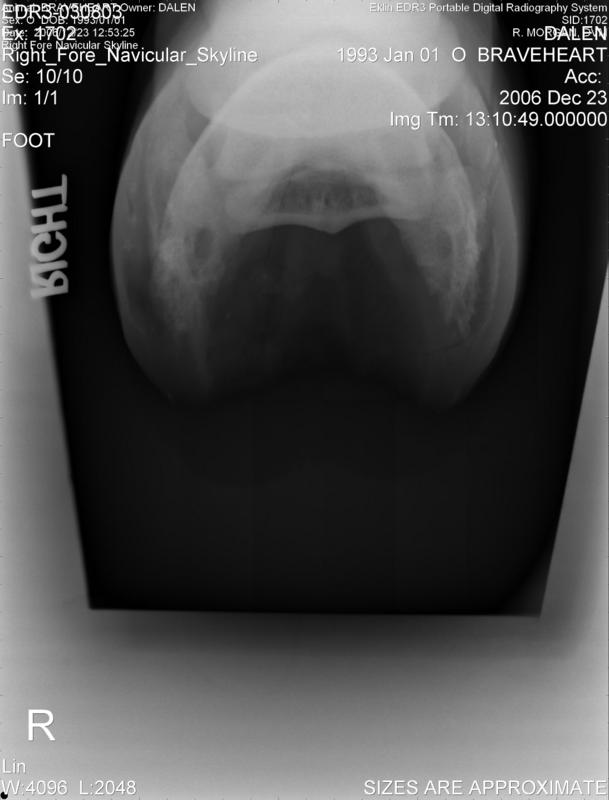

Posted on Thursday, Jan 4, 2007 - 10:35 am: Thank you, you all have warmed my heart He played with each and every one of his toys yesterday....they were EVERYWHERE .. lol... so yes, I think he's happy The vet said I could try two things. The first is the shoeing... the only different thing we'd do is expand the shoe so it didn't wrap around his heel. His current shoe (that he's had since November 21) wraps around his heel, the September/October shoe did not. This happened before (about 6 months or so ago) and he went lame, I had her adjust the shoe so it didn't wrap around and he went sound. It's a reach, but the vet says it's worth a shot for one shoeing. Then we go to the rock n roll or rollermotion (only if the vet approves). Thank you Dr. O, I will print out your article and show it to my farrier. He didn't tell me what lesions he had. Here are a couple of xrays: Right front skyline Right front

|

Posted on Friday, Jan 5, 2007 - 10:13 am: Thank you Lynn Dr. O, can you tell by these xrays if there are erosions on the flexor surface? What is the flexor surface? Thank you. |

Posted on Saturday, Jan 6, 2007 - 8:36 am: Lee, I could not help myself so I peaked, in my opinion neither the improved condition or the acute bow are likely to be do to the magnets.Aileen there is a suspicious spot in the navicular's flexor side, just medial to the midline and I almost think I can see a actual defect in the surface but this may be artifactual. It is the darkening seen in the bone just to the left of the light pointy down area in the middle of the radiograph. When I get in the office on Monday I will view it on my large screen and see if I can put an error on it. DrO |

Posted on Thursday, Jan 11, 2007 - 6:06 am: Aileen, I don't see anything to suggest this is metatsized cancer. Your last veterinarian, and the last radiograph you posted support his diagnosis, that your horse suffers from chronic heel pain do to a diseased navicular bone. The radiograph appears to show a erosion on the flexor surface so we have at least two areas causing pain: the eroded navicular bone and the damage it does to the the flexor tendon. There are no effective treatments if this is in fact the cause though the article on navicular disease gives some ideas to help lower the discomfort.To further nail this down you could have a navicular bursa block and if it blocks out here ultrasound (demonstrate soft tissue damage and the outline of the erosion), a series of skylines (to define the extent of the erosion), and/or MRI (may show both in great detail) of the foot done. DrO |